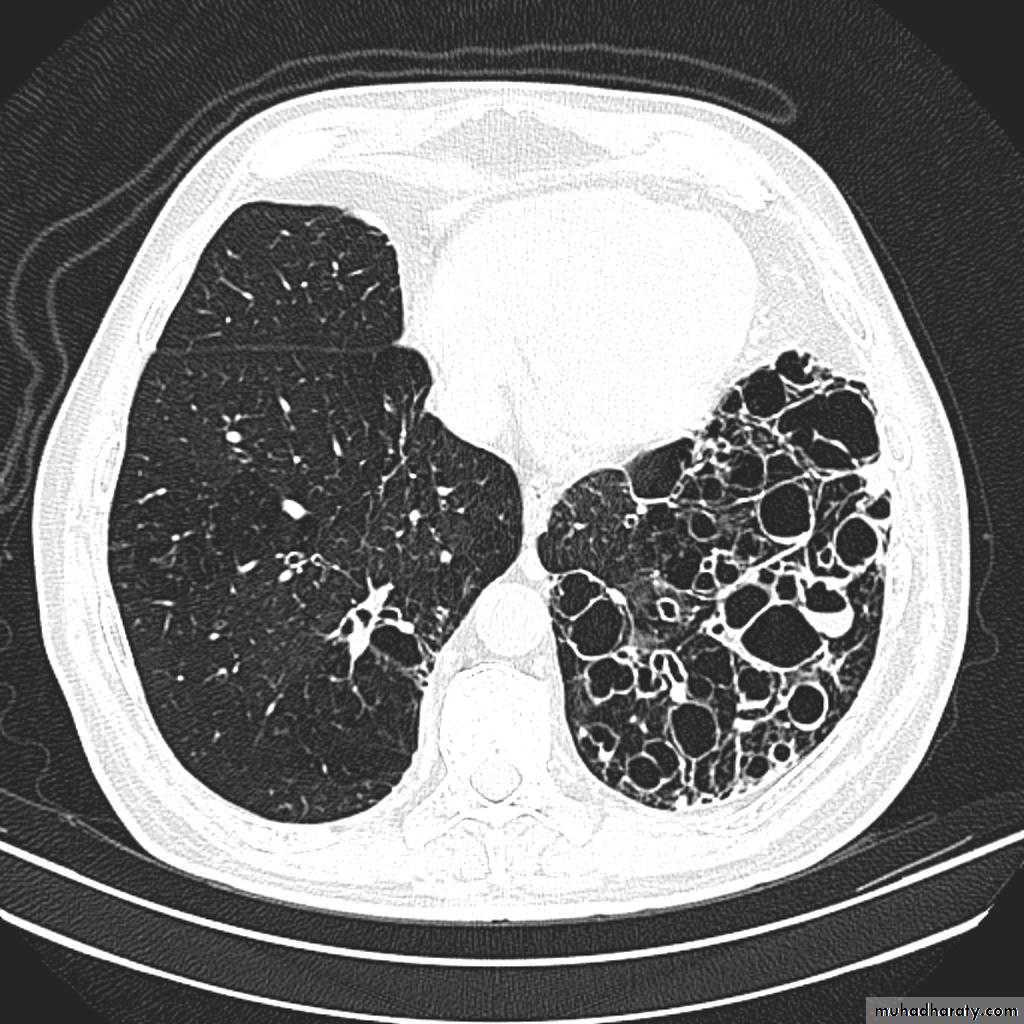

Bronchiactasis

Bronchiectasis refers to abnormal dilatation of the bronchial tree and is seen in a variety of clinical settings. CT is the most accurate modality for diagnosis. It is largely considered irreversibleCauses of bronchiactasias very important to consider

Plain radiograph

Chest x-rays are usually abnormal

1. Tram-track opacities are seen in cylindrical bronchiectasis, and

2. air-fluid levels may be seen in cystic bronchiectasis.

Honey comb shadow

3.Overall there appears to be an increase in bronchovascular markings, and bronchi seen end on may appear as ring shadows .

4.Pulmonary vasculature appears ill-defined, thought to represent peri bronchovascular fibrosis .